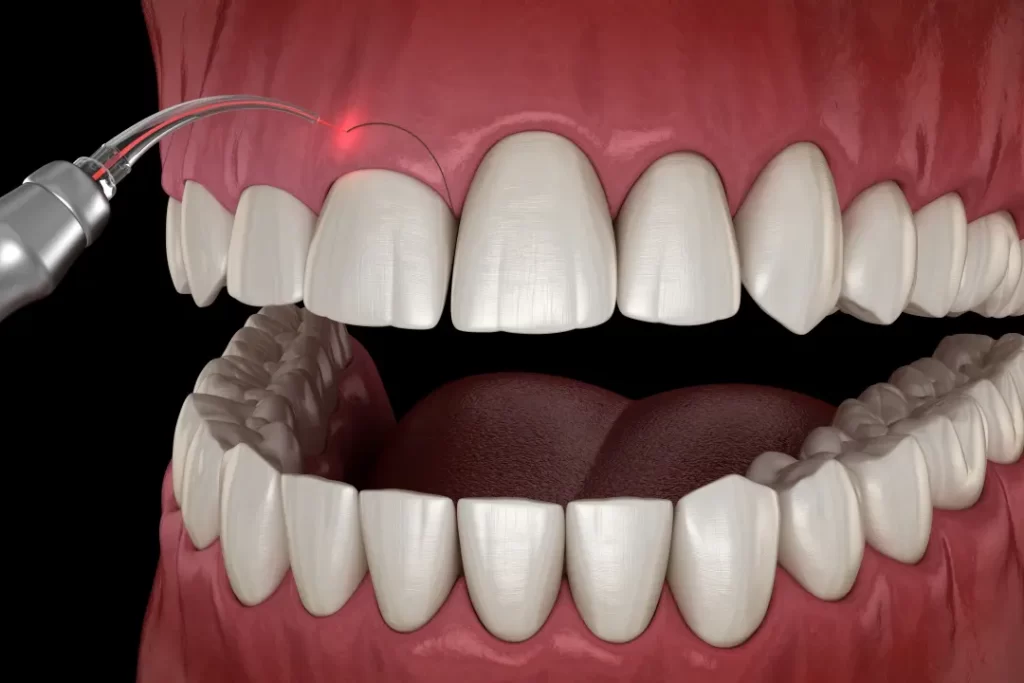

QUY TRÌNH CẮT CHÓP Răng

- 3. Gây tê, tiếp cận và cắt chóp chân răng: Trước khi bắt đầu quy trình, vùng cần điều trị sẽ được gây tê để đảm bảo bạn không cảm thấy đau hoặc khó chịu trong suốt quá trình điều trị. Bác sĩ sẽ tạo đường vào vị trí chóp răng bị nhiễm trùng, loại bỏ khoảng 2mm phần chóp răng, đồng thời làm sạch mô viêm xung quanh.